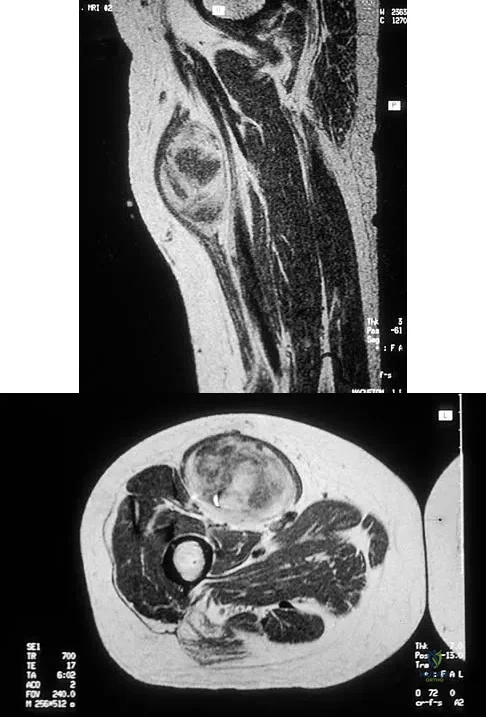

A 51-year-old male truck driver has had progressive left hip pain for more than 2 years, and he reports that the pain has become severe in the past 9 months. He is now unable to work because of the pain. Examination reveals that range of motion of the hip is limited to 95 degrees of flexion, 0 degrees of internal rotation, and 20 degrees of external rotation. The plain radiograph, MRI scan, and intraoperative gross photographs are shown in Figures 9a through 9d. Management should consist of

The diagnosis is synovial chondromatosis. While the plain radiograph fails to show any calcifications, the MRI scan shows an intra-articular mass that involves the capsule. Grossly multiple granular cartilage nodules are seen. Management should consist of removing all loose bodies along with the synovial membrane.